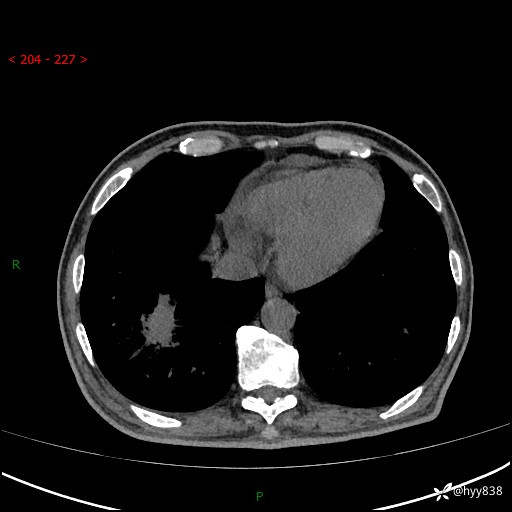

【患者信息】:66岁/男

【主诉】:确诊髓系白血病5月余,乏力纳差伴气促半月

【检查】:胸部CT平扫